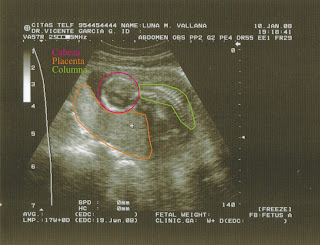

Diagnóstico:

"Útero gestante que presenta un feto único con latido cardíaco positivo y buena movilidad.

La placenta se encuentra implantada en fúndica posterior y sus características ecográficas se corresponden con la edad gestacional de la paciente.

Líquido amniótico normal.

Según diámetro biparietal la edad gestacional aproximada es de 19 semanas y 1 día, según la longitud del fémur la edad gestacional aproximada es de 19 semanas y según la circunferencia abdominal la edad gestacional aproximada es de 19 semanas. Según los parámetros biométricos la edad gestacional es de 19 semanas y 1 día.

Según el tiempo de amenorrea la edad gestacional es de 20 semanas.

El peso fetal estimado es de 231 gramos.

Se estudia el flujo mediante señal Doppler color y pulsado, obteniéndose registros a nivel de arteria y vena umbilical, aorta fetal, arteria cerebral media y arterias uterinas.

Los valores obtenidos quedan reflejados en la placa.

Las curvas obtenidas muestran una morfología normal y los valores de la ratio e índices de resistencia se encuentran dentro de los límites normales.

Impresión diagnóstica: Eco-Doppler obstétrico sin hallazgos de significado patológico, no existiendo en el momento actual signos de sufrimiento fetal.

Estudio morfológico dentro de la normalidad."